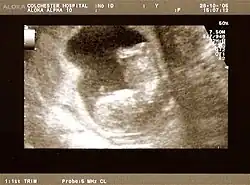

The result of an ultrasonography: a black and white image that shows a clear view of the interior abdomen

A dating scan at 12 weeks

Obstetric ultrasonography is routinely used for dating the gestational age of a pregnancy from the size of the fetus, determine the number of fetuses and placentae, evaluate for an ectopic pregnancy and first trimester bleeding, the most accurate dating being in first trimester before the growth of the foetus has been significantly influenced by other factors.[22] Ultrasound is also used for detecting congenital anomalies (or other foetal anomalies) and determining the biophysical profiles (BPP), which are generally easier to detect in the second trimester when the foetal structures are larger and more developed.[23]

X-rays and computerized tomography (CT) are not used, especially in the first trimester, due to the ionizing radiation, which has teratogenic effects on the foetus.[24] No effects of magnetic resonance imaging (MRI) on the foetus have been demonstrated,[25] but this technique is too expensive for routine observation. Instead, obstetric ultrasonography is the imaging method of choice in the first trimester and throughout the pregnancy, because it emits no radiation, is portable, and allows for realtime imaging.[26]

The safety of frequent ultrasound scanning has not been confirmed. Despite this, increasing numbers of women are choosing to have additional scans for no medical purpose, such as gender scans, 3D and 4D scans.[27] A normal gestation would reveal a gestational sac, yolk sac, and fetal pole.[28]

The gestational age can be assessed by evaluating the mean gestational sac diameter (MGD) before week 6, and the crown-rump length after week 6. Multiple gestation is evaluated by the number of placentae and amniotic sacs present.[29]